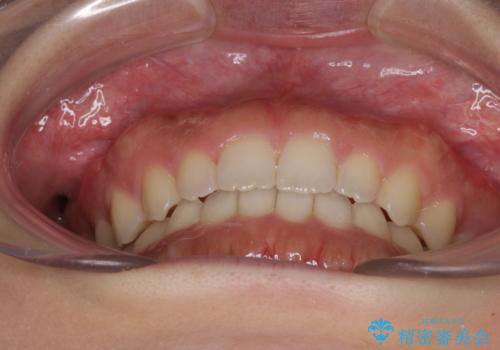

気になる隙間の再矯正 前歯をインビザライン・ライトで改善

- 後戻りによる上下前歯の隙間を気にして来院された患者様です。

歯列不正はそれほど大きくなかったため、インビザライン・ライトを用いて矯正治療を行うこととしました。

無理のないペースで治療を進め、9ヶ月で終えることができました。